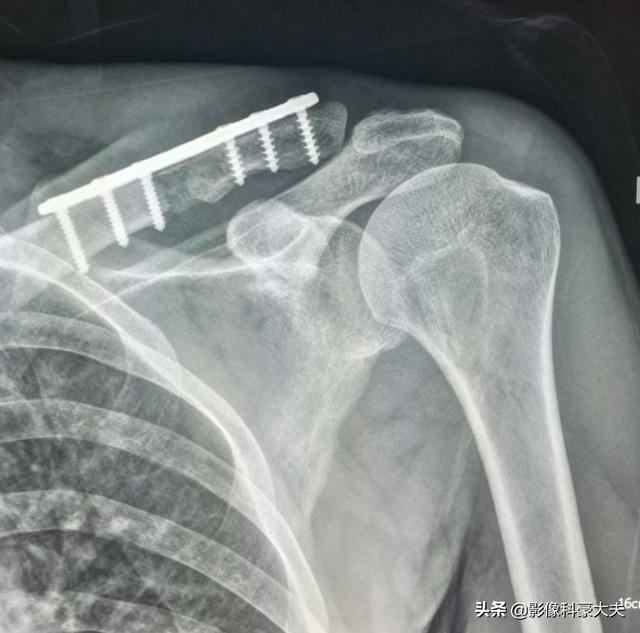

これは、当時彼が鎖骨骨折のために受けた内固定手術で、手術をしなければ自然治癒が非常に難しい病的骨折である。